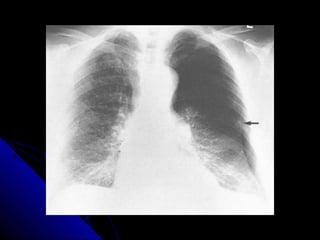

PPnneeuummootthhoorraaxx// tteennssiioonn

45

ppnneeuummootthhoorraaxx

CChheecckk tthhee tteecchhnniiccaall qquuaalliittyy..

TThhee aabbnnoorrmmaall ssiiddee hhaass << vvaassccuullaarr mmaarrkkiinnggss..

LLooookk ffoorr lluunngg eeddggee..

LLooookk ffoorr mmeeddiiaassttiinnaall sshhiifftt..

AAsskk ffoorr eexxppiirraattoorryy ffiillmm..